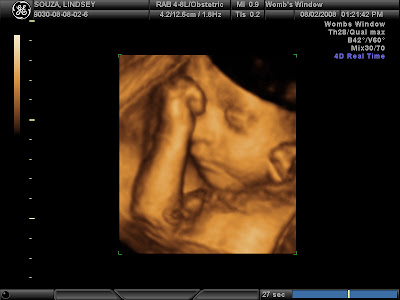

He was asleep when she started the scan but only took a moment to wake right up. And begin poking and jabbing and kicking at the pressure of the ultrasound wand thing. After about 30-35 minutes of being in perfect position for pictures and us seeing his face, he promptly rolled over to face my back then she REALLY had to work to get shots of him, including asking me to eat candy (Travis got a piece too). He was set on being stubborn though and wouldn't flip back over so after about 10 minutes of seeing what we could like he was, we called it a day. It was only supposed to be 30 minutes so I had no complaints. He kept his hands up around his face. Sometimes over it, sometimes just in front of it. Occasionally a foot would pop up there also. As you'll see in the pictures, he would OPEN HIS EYES some too. Travis really liked that. All in all, we were all amazed and it was worth every cent to do it. I wanted to put some of the dvd on here, but ummm, video conversion isn't my strong point and I've already got 1 email asking where are the pictures, so I'm just going to put them up here for now! Here are my favorites:

See his eye open?